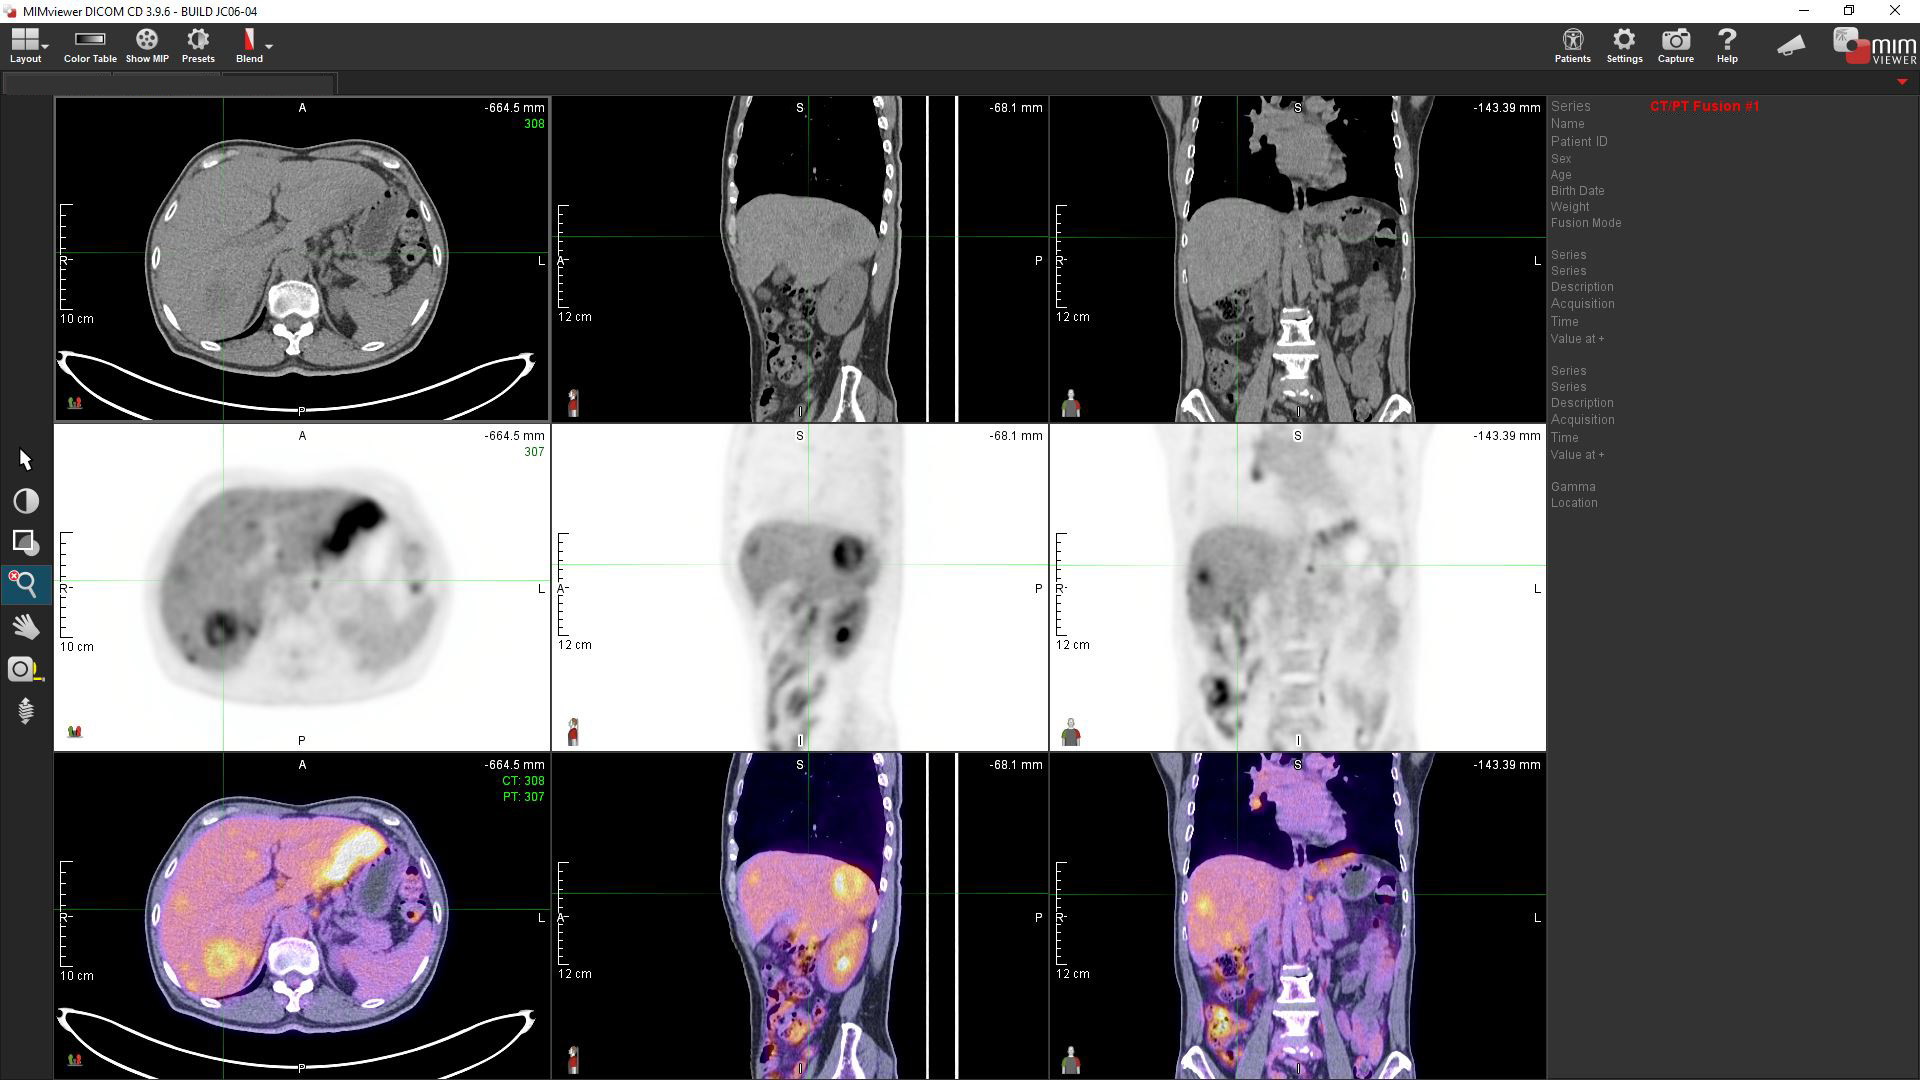

我的主诊医生需要电子版本的影像及报告,你们能提供吗?

除实体彩色印刷本外,报告内亦会附上USB储存装置,内存DICOM 断层影像及由核子医学专科医生编撰的病理图片。利用已载入的专业影像浏览软件MIM Viewer,主诊医生及病人便能使用一般个人电脑来检视双融影像,并载入电脑作治疗计划用途。您亦可申请将影像及报告上载到政府的电子健康纪录互通系统(医健通),供参与计划的医疗机构查阅。